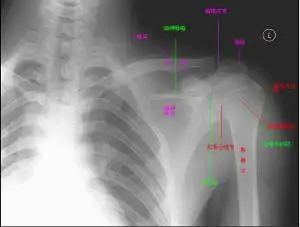

肩关节平扫是为了明确肩关节病变而做的ct的基本检查方法,对于病变的